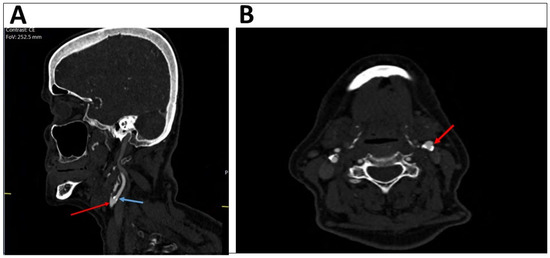

A comparison of the degree of stenosis of the internal carotid artery by DUS and CTA (Table 2) showed that out of the patients with less than 50% occlusion on CTA (the gold standard), 90.8% were also identified as having less than 50% stenosis by DUS. Among the patients with stenosis of 70% or more on CTA, 73.3% showed the same result on the DUS. Out of the patients with 50–69% stenosis found by CTA, 45.5% of them had different percentage of stenosis by DUS. An example of different results for a single patient shown by DUS and CTA can be seen in Figure 1 (presenting DUS results) and Figure 2 (presenting CTA results).

Figure 2.

CT angiography showing the same patient with mild stenosis of the left internal carotid artery. The sagittal plan (A) presents the left common carotid artery (bulb, red arrow) and the left internal carotid artery (blue arrow). The axial plan (B) shows mild stenosis of the left internal carotid artery (red arrow).